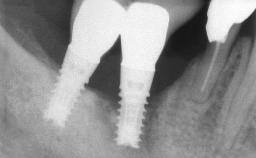

Peri-implantitis Modified by Submucosal Excess of Cement: Regenerative Peri-implantitis Therapy and Six-year Follow-up

A 30-year-old female patient was referred to the Department of Periodontology of the University of Bern, Switzerland, by a dentist in private practice. Tooth 45 had been congenitally missing and had been replaced with a titanium implant three years prior to the first visit at the Department of Periodontology. The tissue level implant had a diameter of 4.1 mm, a length of 12 mm, and a sandblasted and acid-etched (SLA) surface (Straumann® Dental Implant System; Institut Straumann AG, Basel, Switzerland). The metal-ceramic crown on implant 45 had been cemented permanently. Implant 45 had been diagnosed with peri-implantitis by the referring dentist in the course of regular supportive care.